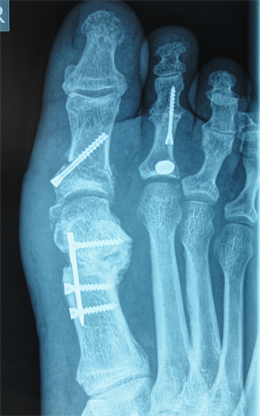

Figure 7. Patient Nr. 2. Hallux valgus with subluxed Ist MPJ and pathological DMAA.

Figure 8. Patient Nr. 2: Correction with 100% lateralization and only point contact of the osteotomy partners.

Figure 9. Patient Nr. 2. Result after 7 years. All components are corrected, no loss of lenght. Immediate full weight bearing, running after 8 weeks.